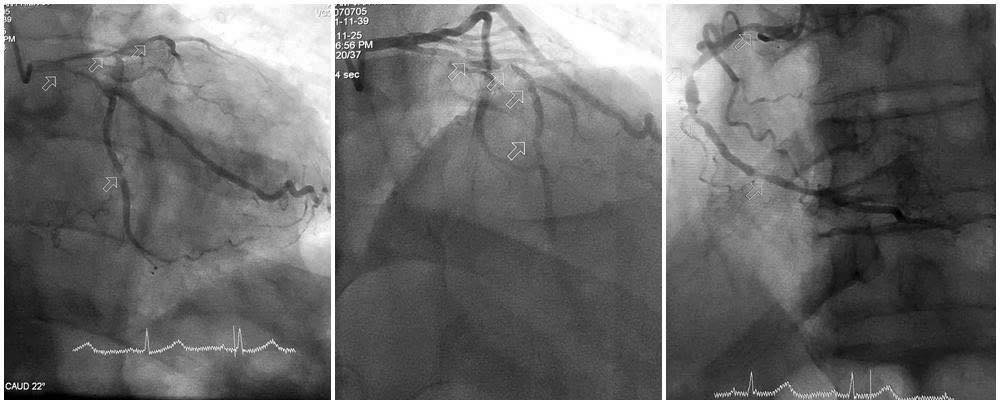

Hình ảnh tổn thương nặng 3 thân động mạch vành - Ảnh BVCC

Kết quả chụp mạch vành cho thấy mức độ tổn thương nặng cả ba thân động mạch vành. Động mạch liên thất trước hẹp tới 90–99%, gần như tắc hoàn toàn; động mạch mũ và động mạch vành phải hẹp 80–90%, thành các mạch vôi hóa nhiều.

TTƯT.BSCKII Trần Quang Định, Trưởng khoa Phẫu thuật và Can thiệp Tim mạch, Bệnh viện Đa khoa tỉnh Quảng Ninh đánh giá: Đây là ca can thiệp khó. Người bệnh đã ở tuổi 86, thể trạng gầy yếu, lại rơi vào tình trạng sốc tim. Hệ mạch vành vôi hóa nặng khiến việc đưa dây dẫn và dụng cụ qua các tổn thương tiềm ẩn nhiều nguy cơ.